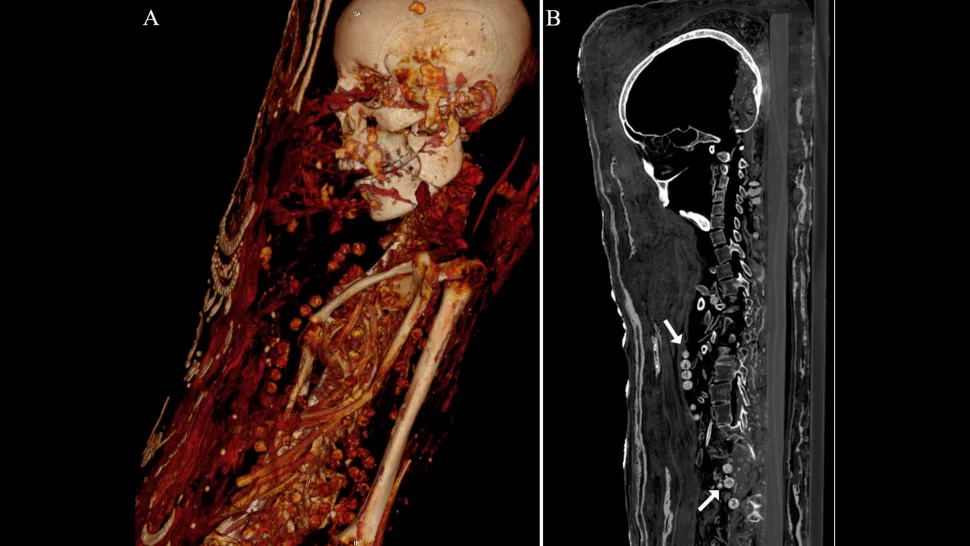

Mężczyzna zmarł między 25. a 30. rokiem życia. Miał 164 cm wzrostu, dwa niewyrwane zęby i kilka ubytków. Niektóre z jego kości były złamane i roztrzaskane, prawdopodobnie dlatego, że ktoś naruszył szczątki krótko po odkryciu mumii. Co ciekawe, jego mózg – podobnie jak starszej kobiety – zostały usunięty. Organ ten zachował się jednak u nastolatki.

Ta zmarła między 17. a 19. rokiem życia i miała około 156 cm wzrostu. W jej kręgosłupie wykryto łagodną formę guza. Starsza kobieta, która zmarła między 30. a 40. rokiem życia, miała około 151 cm wzrostu. Dokuczało jej zaawansowane zapalenie stawów w lewym kolanie. Obie zostały wyposażone w zdobione naszyjniki, co sugeruje, że były przedstawicielkami wyżyn społecznych.